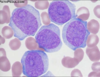

Name the stages of development shown here.

- proerythroblast (aka pronormoblast)

- basophilic erythroblast/normoblast

- polychromatic erythroblast/normoblast

- orthochromatic erythroblast/normoblast

- reticulocyte (aka polychromatic erythrocyte)

- erythrocyte